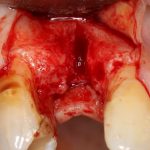

Рекомендации по установке имплантов. Для всех. Часть V.